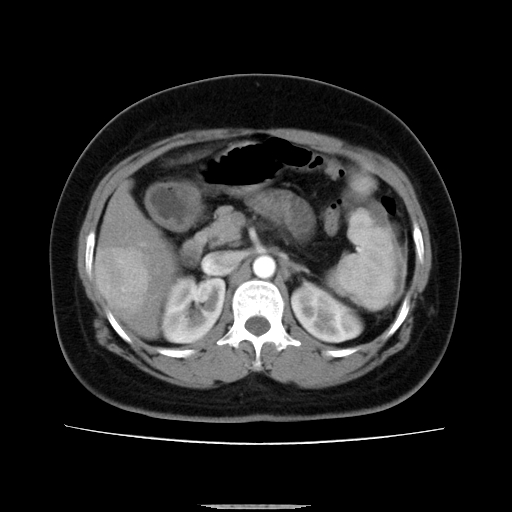

标题: CT14225:女性46岁。当地B超示肝内占位,来我院作CT检查。请 [打印本页]

标题: CT14225:女性46岁。当地B超示肝内占位,来我院作CT检查。请

速升速降,支持肝癌.脾体积增大,形态欠规整,请询问病史是否做过脾动脉栓塞.

速升速降,支持肝癌可能。

快进快出,符合肝癌表现-----------

肝内结节强化特点符合原发性肝癌表现,脾脏改变考虑为增大及先天发育所致。

肝内结节强化特点:快进快出符合原发性肝癌表现

此患者虽然符合快进的特点,却不符合快出的特点,因为门脉期几乎是等密度,不符合肝癌的增强表现,所以我考虑肝局灶性结节增生可能性大